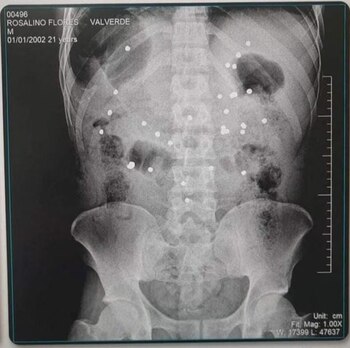

El ensañamiento contra Rosalino Flórez, de apenas 22 años, también causó conmoción en la población. El joven recibió 36 perdigones en la espalda, disparados por un policía en Cusco. El hecho lo dejó inconsciente y entubado durante 11 días en el hospital Antonio Lorena del Cusco.

Pasó por tres operaciones para lograr extirparle solo 14 de las balas alojadas en su cuerpo, le redujeron los intestinos al mínimo y, finalmente, fue trasladado al hospital Arzobispo Loayza, donde falleció luego de estar en coma por dos meses.